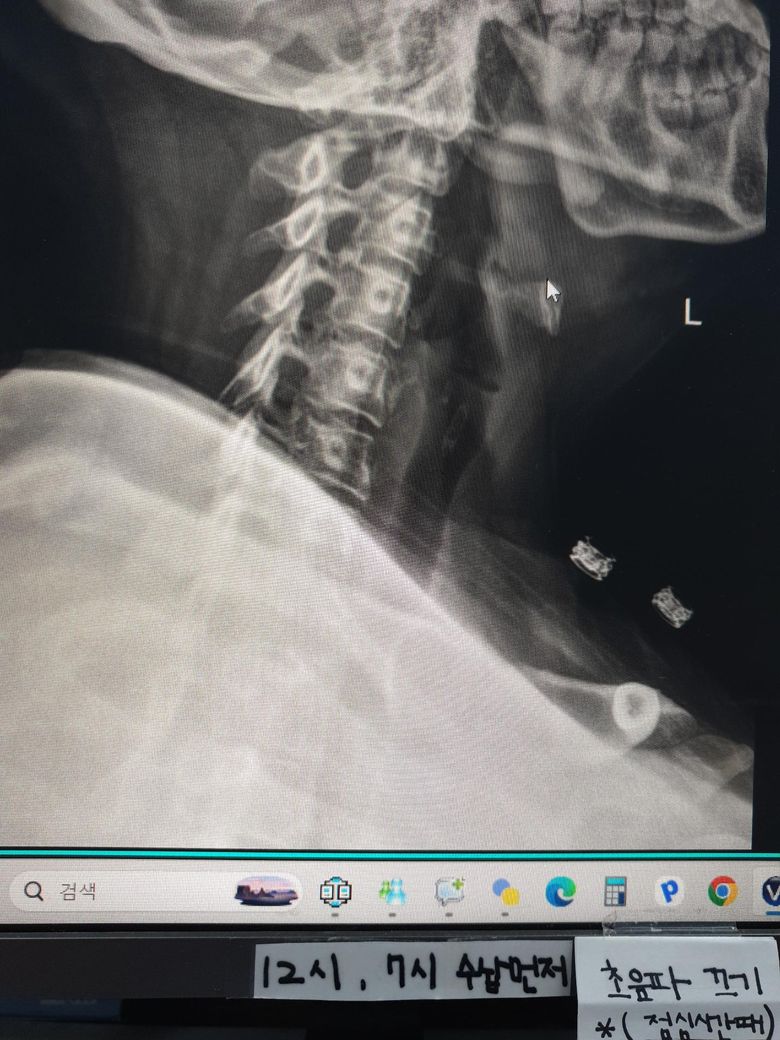

지금 현재 목 상때입니다 지금 오른쪽 목 신경이 시작하는 부분이 많이 아프고(후두동맥 부분) 신경이 뻣치는 느낌이 있어요 가만히 있어도 통증이 있습니다 지금 베개는 안맞는건지 불편해서 깨거나 신경시 뻣치는 느낌이 나서 깨요 가격대는 4만원까지 생각하고 있고 등이랑 어깨가 말려있어서 높이 않으면 숨이 막혀요 옆으로 누워서 자구요

• 3번 째 사진

• 앞선 질문의 추가 답변입니다. 앞서 말씀드린대로 현재 경추 전만 감소와 후경부 근긴장이 중심으로 보이며, 베개 외에도 생활요인이 통증 지속에 크게 관여합니다. 핵심만 정리드립니다.